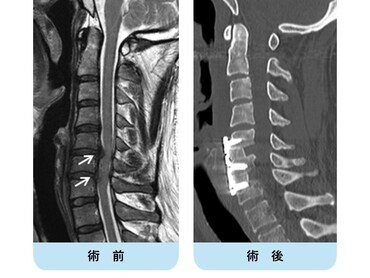

頚椎後縦靭帯骨化症(頚椎OPLL)

頚椎の椎体の後面に脊髄と接している後縦靱帯が骨化して、脊髄を圧迫する疾患です。進行すると脊髄圧迫による頚部や肩の痛み、手足のしびれ、手指の巧緻運動(細かい作業)障害、歩行障害などを生じます。

脊髄の圧迫の程度を評価するにはMRI検査が有効です。症状が軽い場合は、装具療法、薬物療法などの保存療法を行います。手指の巧緻運動障害や歩行障害が出てきた場合には、手術が必要となる可能性が高いです。

手術は前方から骨化を取り除き、骨を移植して固定する前方除圧固定術と、後方から椎弓を形成して脊髄の圧迫を解除する椎弓形成術があります。また、症状がないか軽くても転倒などの怪我で脊髄麻痺を生じることがあるので注意が必要です。なお厚生労働省特定疾患として認められています。

頚椎OPLLを認め脊髄を圧迫している状態です。前方からの骨化浮上術により症状は改善しています。

頚椎椎間板ヘルニア

頚椎の疾患の中で頻度の高い病態の一つです。症状はヘルニアの突出方向によって異なります。一般的には左右どちらかに偏って突出することが多く、脊髄から分岐した片側の神経根(神経の枝)を圧迫することにより、片側の頚部から肩及び肩甲骨や腕などの痛みやしびれを生じ、筋力低下を呈することもあります。また、中央に大きく突出した場合には、脊髄の本幹を圧迫することにより、手指の細かな運動がしづらい、歩行障害や膀胱直腸障害(頻尿、尿閉、尿失禁など)などの症状が出現します。

治療は保存的加療が中心ですが、脊髄や神経根の圧迫による神経障害が出現した場合には早期に手術を要する場合もあります。

頚椎椎間板ヘルニアを認め脊髄(灰色)を圧迫している状態です。骨移植を伴う頚椎前方固定術により症状は改善しています。